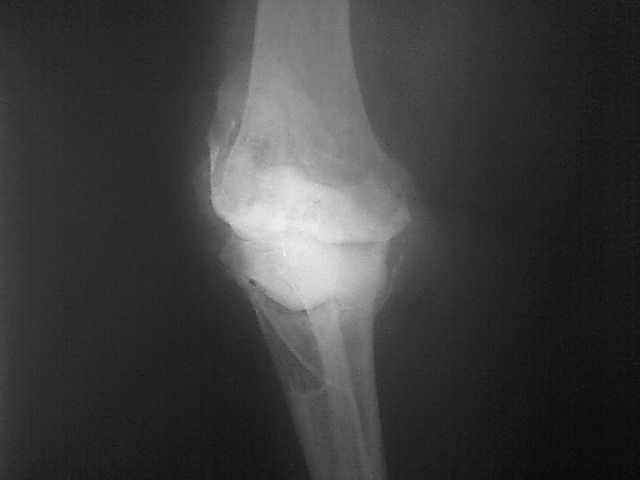

Женщина 1952 г.р., оперирована в 2006, в одной клинике установлен эндопротез правого коленного сустава, через год нестабильность обоих компонентов, доктор выполняет ревизию обычным протезом с задним стабилизатором.

В октябре 2008 - нестабильность, свищ. В другом стационаре все удалено, спейсер с гентамицином, длинный курс антибиотиков.

Коллатеральных связок нет. Собственная связка надколенника цела.

До удаления протеза - выраженная смешанная контрактура.

Планы: Стоит выбор 1) Обычный hinge с цементными ножками, вставками под тибиальным и бедренным компонентами с импакционной костной пластикой аллокостью с применением сеток для удержания трансплантата на tibia; 2) Онкологический hinge - с замещением проксимальной голени и сохранением бедра; 3 - артродез.